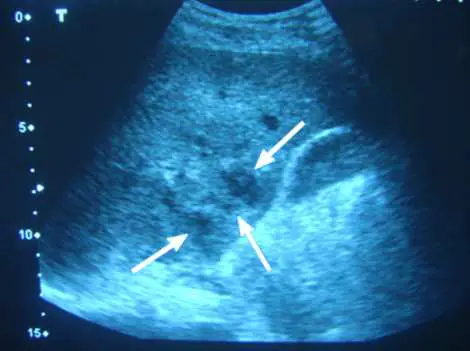

下圖為肝臟之超音波掃描圖,箭號所指處最不可能的病灶為:

本題為反向題(問「最不可能的病灶」),考查肝臟超音波(liver ultrasound)對局部病灶(focal liver lesion)的鑑別診斷能力。重點在於辨識各種肝臟病灶的超音波特徵,並找出最不可能的診斷。

肝臟超音波影像所見:

- 探頭方向:標準腹部超音波掃描,顯示肝臟實質

- 病灶特徵(箭號所指處):

- 病灶為不均質(heterogeneous)混合回音,呈現複雜性回音結構

- 病灶邊緣不規則,邊界不清晰

- 內部回音混雜,可見部分低回音(hypoechoic)與較高回音(hyperechoic)區域交錯

- 病灶具有厚而不規則的壁(thick irregular wall)

- 可見內部回音碎屑(internal debris/echogenic content)

- 無明顯後方增強效應(posterior acoustic enhancement)

- 關鍵影像特徵分析:

- 此病灶為複雜性(complex)非均質病灶

- 不符合單純囊腫(simple cyst)特徵:單純囊腫應呈完全無回音(anechoic)、邊界清晰薄壁、有明確後方音影增強(posterior acoustic enhancement)